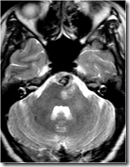

MRI showed signal change in pons and left middle cerebellar peduncle and a heterogenous mass inseparable from the basilar artery in the prepontine cistern…hematoma

A DSA was done which revealed a dissecting aneurysm from the mid-basilar artery jutting to the left side.

Embolisation of the aneurysm was done with GDC coils. The basilar artery was also occluded. All the major braches proximal and distal to the arterial occlusion were filling adequately.